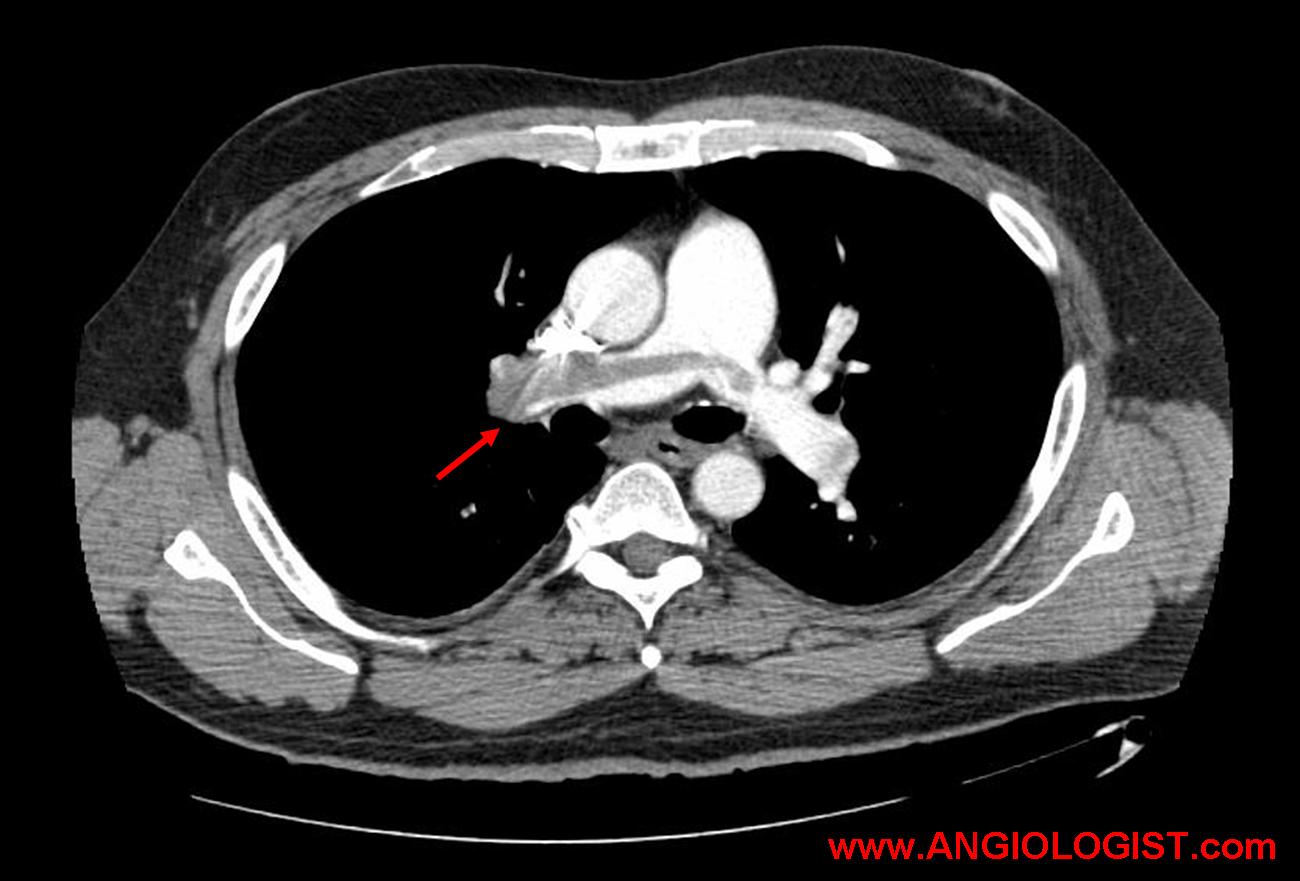

So why am I calling pulmonary emboli a false vascular emergency? Well, I am eluding to the way some patients with pulmonary emboli are being treated. Sometimes patients with pulmonary embolism are treated much more aggressively than their situation mandates. Most patients with pulmonary embolism will do just fine when treated with anticoagulation. Some less common patients obviously need thrombolysis. These are true vascular emergencies and are hard to miss. But there is a group in the middle of patients with submassive pulmonary emboli. The treatment of these patients represents a debate. But because of submassive pulmonary emboli, some patients with low-risk pulmonary emboli are still being treated very aggressively as if they were a vascular emergency. Sometimes these patients suffer unneeded complications. Sometimes imaging drives treatment instead the patient’s clinical presentation. For instance, the saddle PE in the picture above may or may not represent a patient with massive PE. It may or may not represent a true vascular emergency. Complications caused by over zealous clinicians, on the other hand may represent such emergencies…